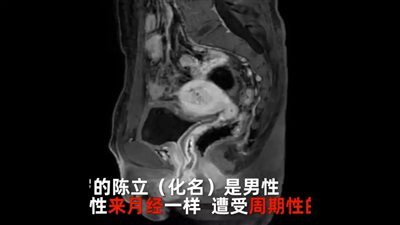

واقعة نادرة | يحيض منذ سنوات.. رجل صيني يكتشف وجود رحم ومبيض بداخله

الأحد 10/07/2022 03:49 م